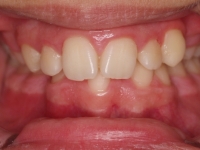

Fotos antes de tratamiento:

El paciente D.M. llega a nuestra consulta sin los 2 premolares inferiores que le quitaron en anteriormente para empezar a mejorar el caso.

– Perfil plano

– Clase III esquelética

– Clase III dental

– Apiñamiento superior muy importante